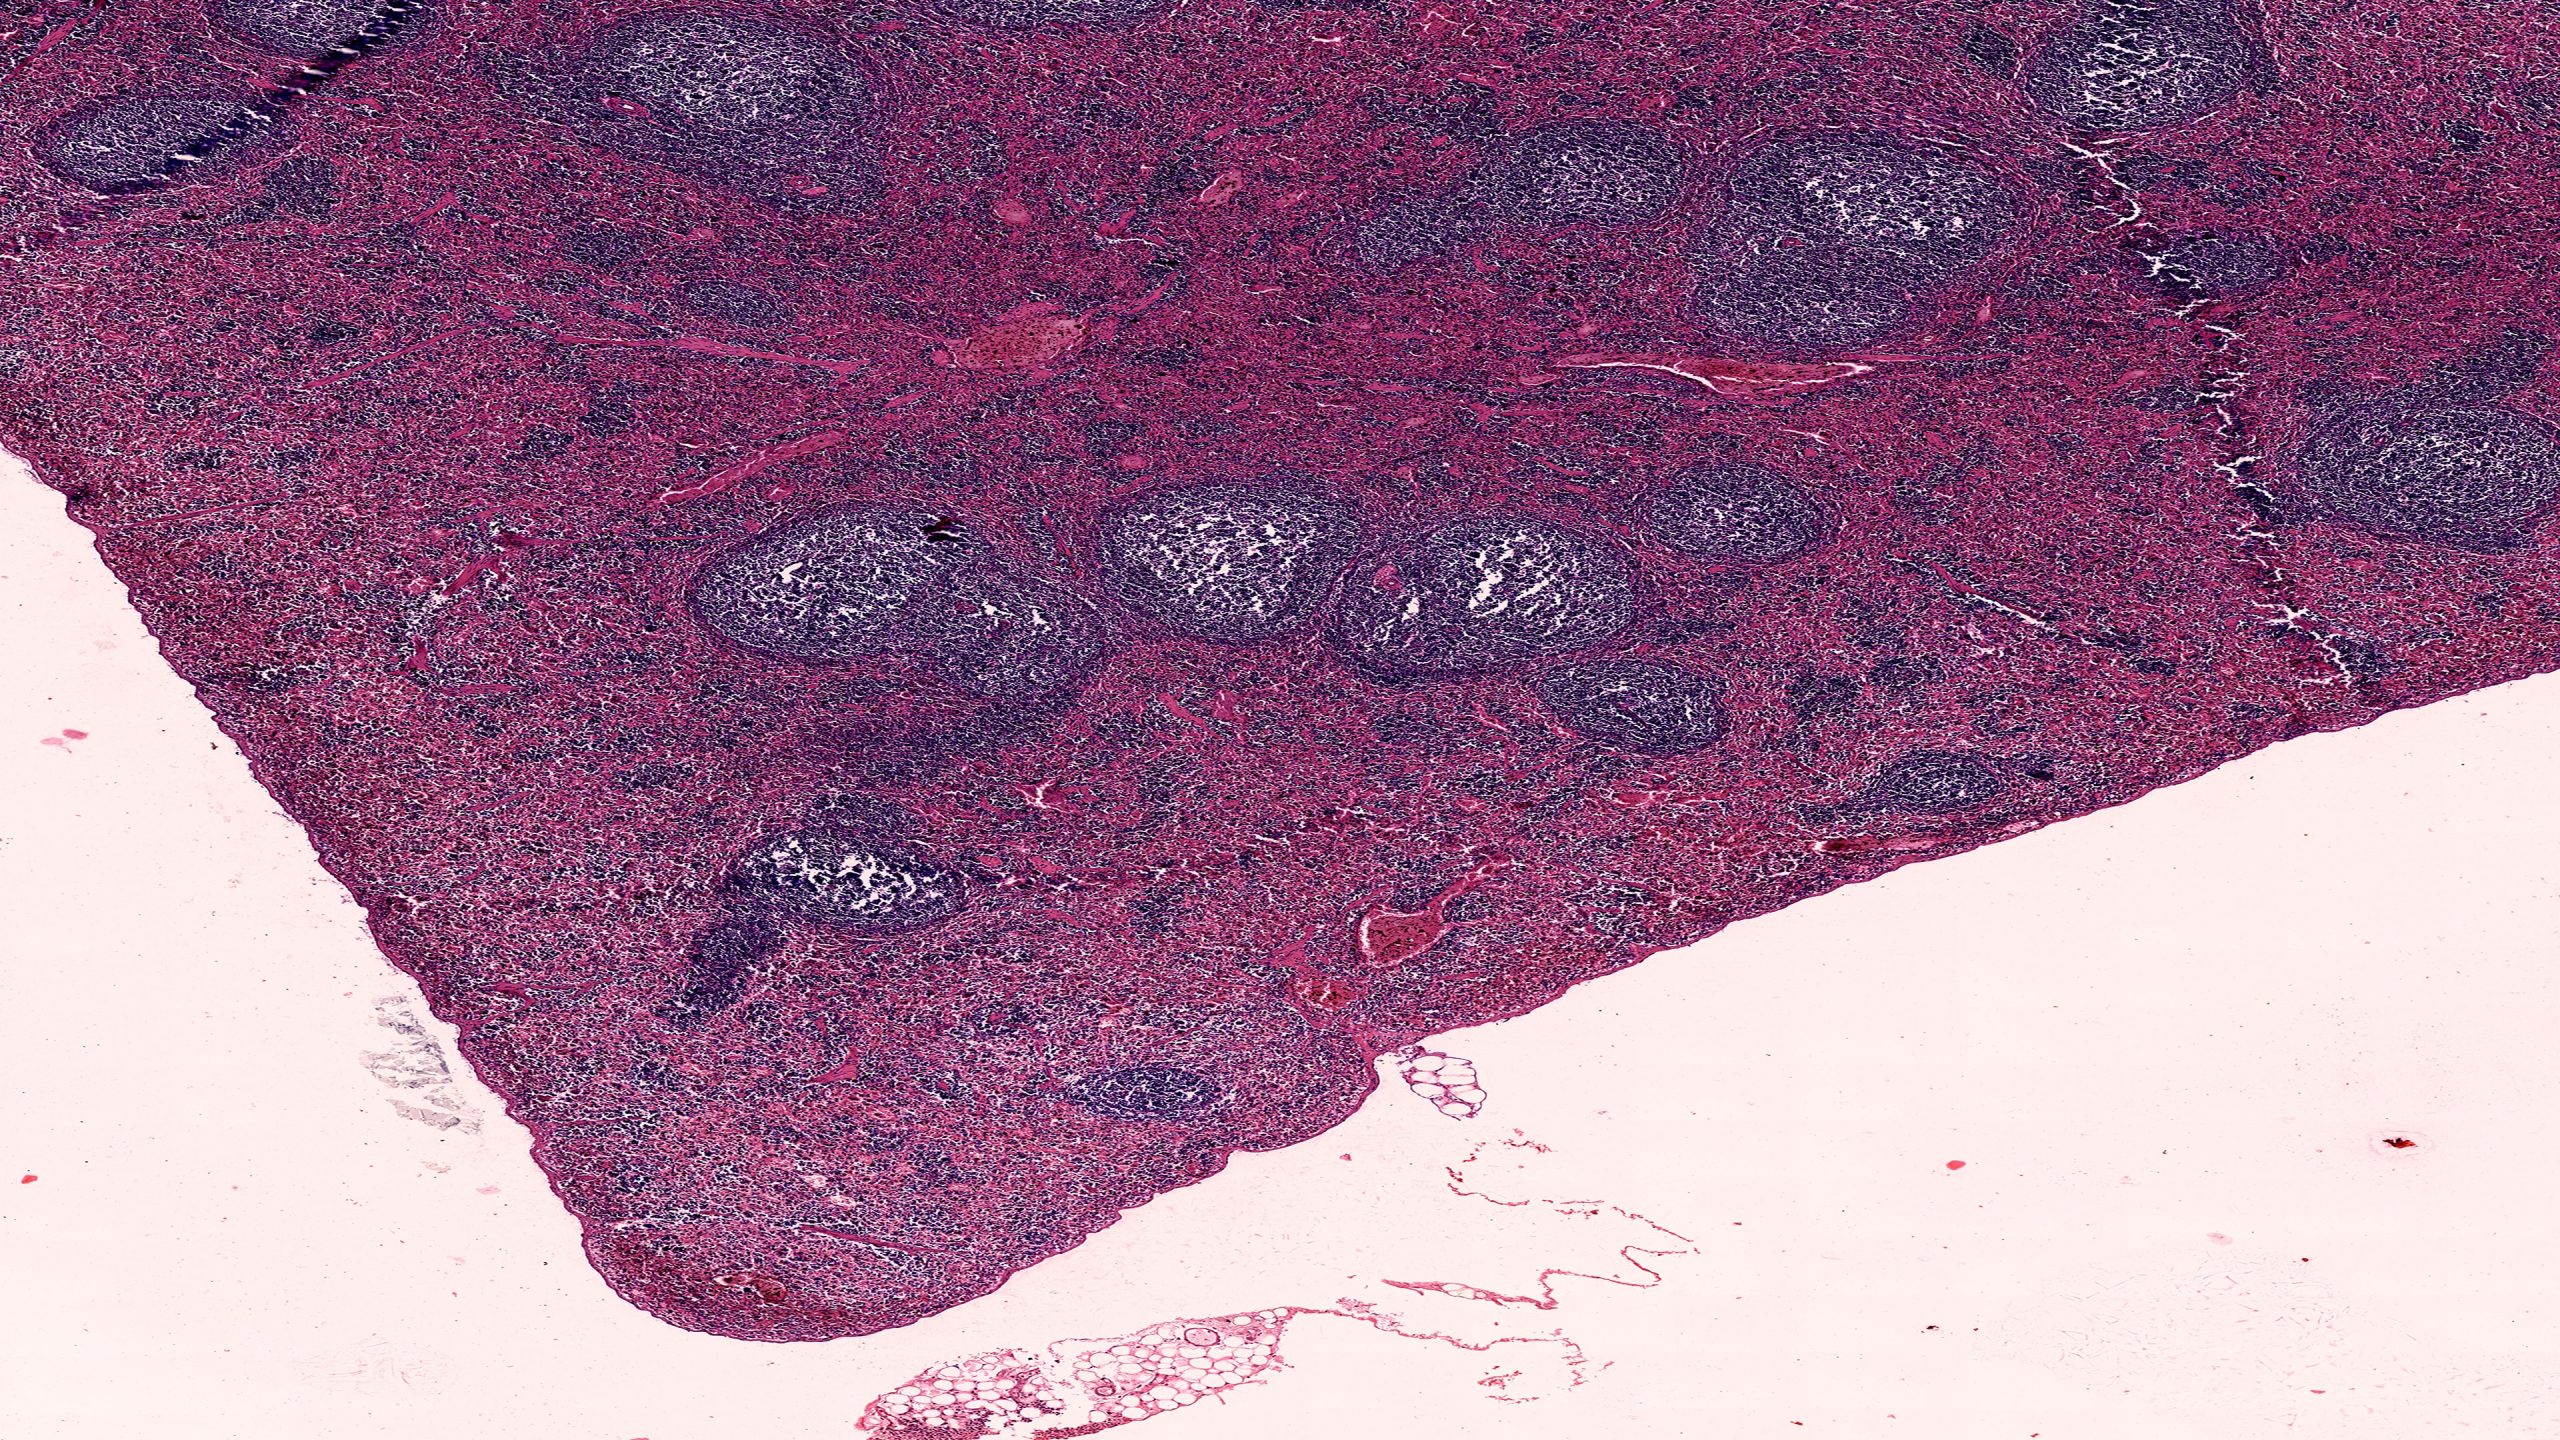

Spleen

Spleen 4X